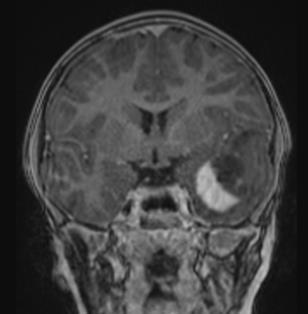

FIGUR 1: MR-bildene viser tydelig heterogenitet i hjernesvulster hos barn. A – Pilocytisk astrocytom i synsnerve (WHO grad ­1); B – Diffust astrocytom (WHO grad – 2); C – Høygradig gliom (WHO grad – 4); D – Diffust midtlinjegliom (WHO grad – 4); E ­ Dysembryoplastisk nevroepitelial tumor (WHO grad – 1); F – Gangliogliom (WHO grad – 1); G – Supratentorielt ependymom (WHO grad – 3); H – Pilocytisk astrocytom (WHO Grad – 1); I – Medulloblastom ( WHO grad – 4); J – Medulloblastom (WHO grad – 4); K – Ependymom ( WHO grad – 4); L ­ Glionevronaltumor forenlig med RGNT ( WHO – Grad 1). Alle pasienter har samtykket til bruk av bildene.